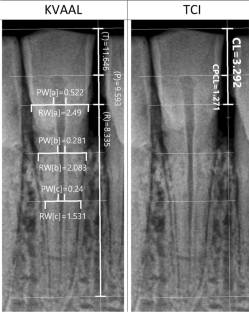

The analyzed material originates from the medieval necropolis of the Vinča—Belo brdo site. During the research, 60 periapical (PA) and 30 orthopantomographic (OPT) images were analyzed. On each analyzed tooth, age assessment was performed using both TCI and Kvaal techniques. The obtained values of dental estimated age were compared with age estimated by anthropological analysis, and the deviations between the estimated and chronological age were analyzed in relation to the assessment technique, type of dental radiograph, tooth group, sex, and age.

The mean error between TCI and the osteological method was 8.44 (SD = 7.56, Min = 0.169, Max = 36.4) and between Kvaal and the osteological method was 7.71 (SD = 5.57, Min = 0.133, Max = 26.7). The average value of age recorded by TCI method was 32.5 years and by Kvaal method was 34.7 years. There was no statistically significant difference based on the two radiographic methods, gender, individual teeth, or tooth group pairs. There was a statistically significant positive correlation between age and the error present.